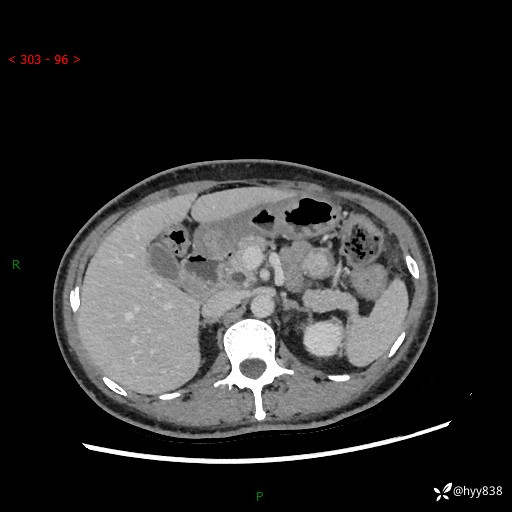

胰腺CT平扫

img